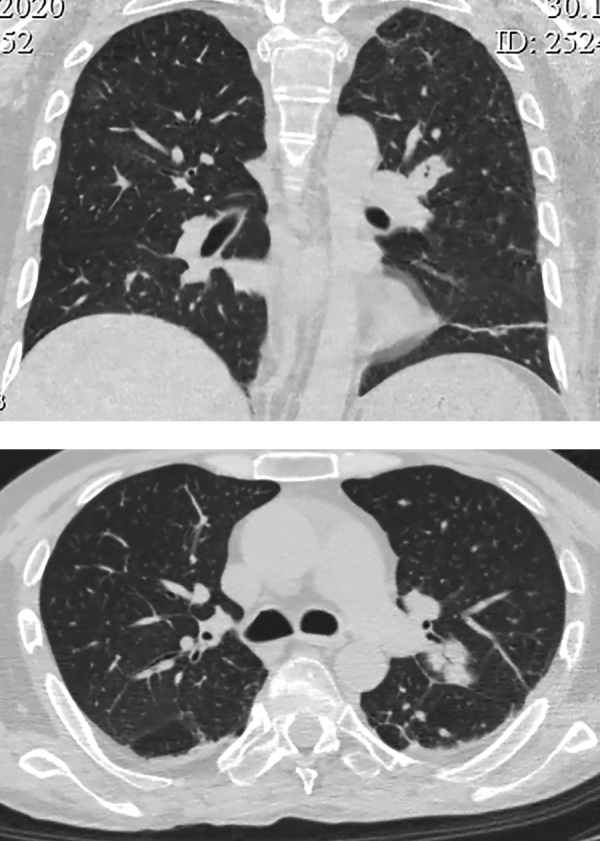

Medullary thyroid carcinoma is a rare aggressive tumor of thyroid gland. Due to its neuroendocrine origine medullary thyroid carcinoma can be the source of ectopic production of different peptides and hormones. We describe a unique case of severe ACTH-dependent Cushing's syndrome due to ectopic corticotropin production by medullary thyroid carcinoma in a male patient of 39 years old with calcitonin level more than 4000 pg/ml (<11,8), thyroid nodule, multiple neck jugular and central lymphnodes. The potassium level was 1,34 mmol/l (3,5-5,1), hypercortisolemia up to 1613,2 nmol/l (185-624) with elevated level of ACTH up to 24,7 pmol/l (1,03-10,74). After the correction of water and electrolytes disorders an operation was performed - thyroidectomy, central and lateral neck dissection. Postoperative calcitonin decreased to 126 pg/ml (<11,8), calcium and parathormone blood levels remained normal. The potassium level didn't decrease without any pharmacological treatment. There was a sharp fall in postoperative blood levels of cortisol and ACTH. The hormonal replacement treatment with hydrocortisone was induced. Morphological examination showed medullary carcinoma with ACTH production in tumor nodule, with metastatic neck lymph nodes. Thus this is a rare case and successful treatment of patient with severe hypercortisolism by thyroidectomy and neck lymphnodes dissection.